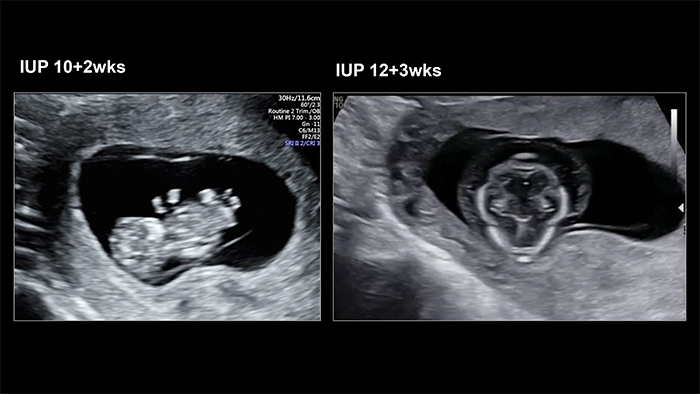

A 44-year-old multigravida woman visited Jeju National University Hospital at 10.2 weeks of pregnancy because of old age. She had a history of autoimmune thyroiditis on medication.

The initial ultrasonography showed weird extremities of the fetus. After that, the clinician diagnosed a conjoined twin with hydrops: one head, one heart, one liver, four arms, and four legs.

Gross examination of the abortus revealed the top of the head down to the belly button, facing each other (cephalopagus).